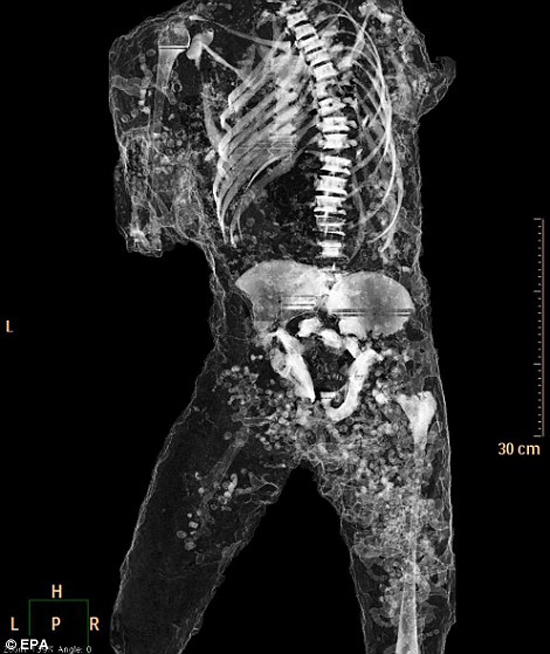

Estos son los primeros sorprendentes detalles que han sido comunicados el 27 de septiembre de 2015, producto de una investigación sin precedentes. Los investigadores han sometido a tomografías axiales computerizadas (TAC) cerca unos 30 cuerpos que fueron encontrados en las excavaciones de Pompeya, los cuales quedaron conservados en moldes de yeso con los que fueron tratados.

Los análisis acaban de comenzar pero los responsables del proyecto explican que con estos exámenes se es capaz de reconocer además de datos normales, como la edad y el sexo, también si era "un fumador de pipa, un músico que tocaba la flauta, así como el origen geográfico o la condición socio económica".

La maquinaria utilizada es una moderna TAC de 16 cortes capaz de hacer un examen de todo el cuerpo en 100 segundos, explican los investigadores. El gran problema es "la densidad del yeso utilizado, pues es muy parecida a la densidad de los huesos y por ello ha sido necesario recurrir a la alta tecnología de una TAC de 16 cortes", explicó hoy el superintendente de Bienes Culturales de Pompeya, Massimo Osanna.